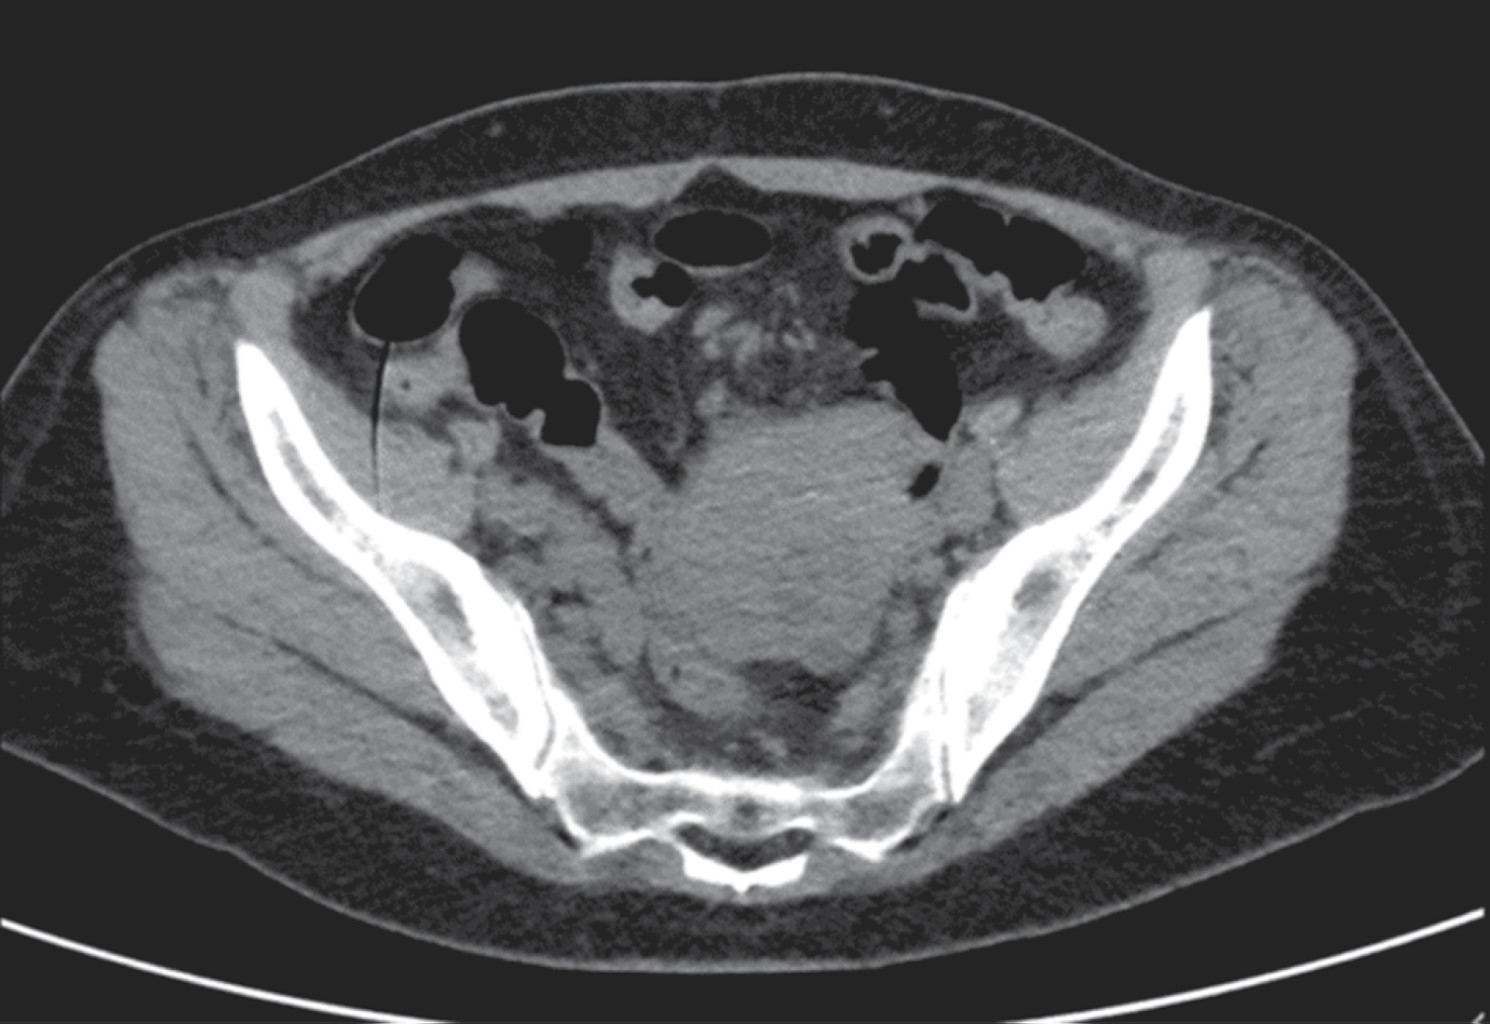

An abdominal ultrasonography (USG) scan was performed, reporting an image of a tumor in the right iliac fossa measuring 10.5 × 5.5 × 9.9 cm. The colonoscopy study showed no evidence of tumor in the rectum and colon, and an apparent extrinsic compression at the ileocecal valve orifice (Figure 1).

A computed axial tomography (CT) scan showed a stenosing and infiltrative tumor of the ileum walls with a narrow lumen and distended bowel loops (Figures 2 and 3).

Figure 2

Figure 3